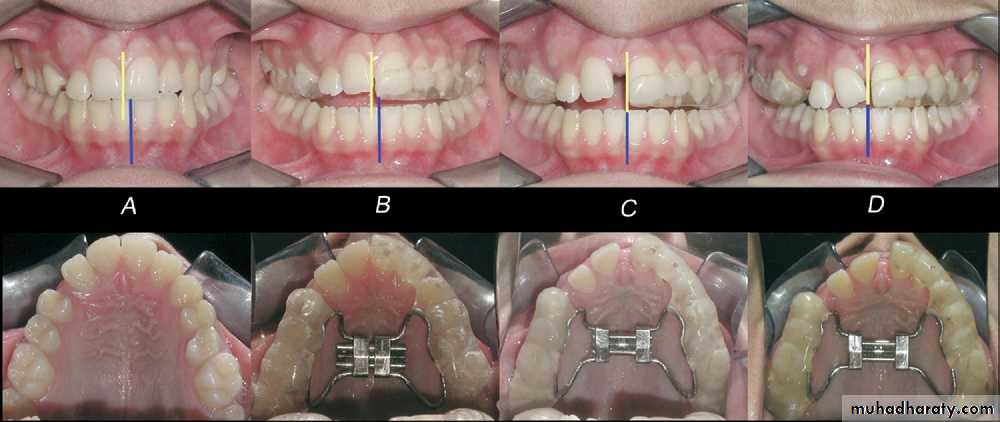

A, Bilateral constricted maxilla with upper midline shift; B, type 1 RME appliance in mouth;

C, end of expansion; D, correction of upper midline shift at end of retention period.